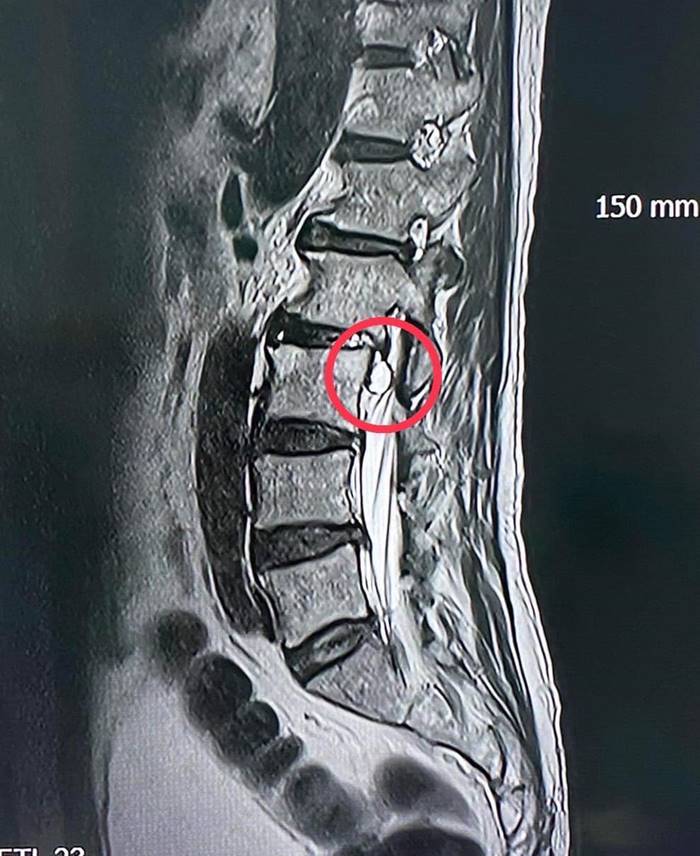

ผลการตรวจสอบจากผู้เชี่ยวชาญด้านศัลยศาสตร์ระบบประสาท คาดว่า เส้นประสาทถูกกดทับ ระดับกระดูกสันหลังข้อที่ 4 จึงส่งตรวจวินิจฉัยโรคเพิ่มเติมด้วย MRI ทำให้เห็นว่ามีก้อนเนื้อไปกดเบียดทับเส้นประสาทอย่างชัดเจน